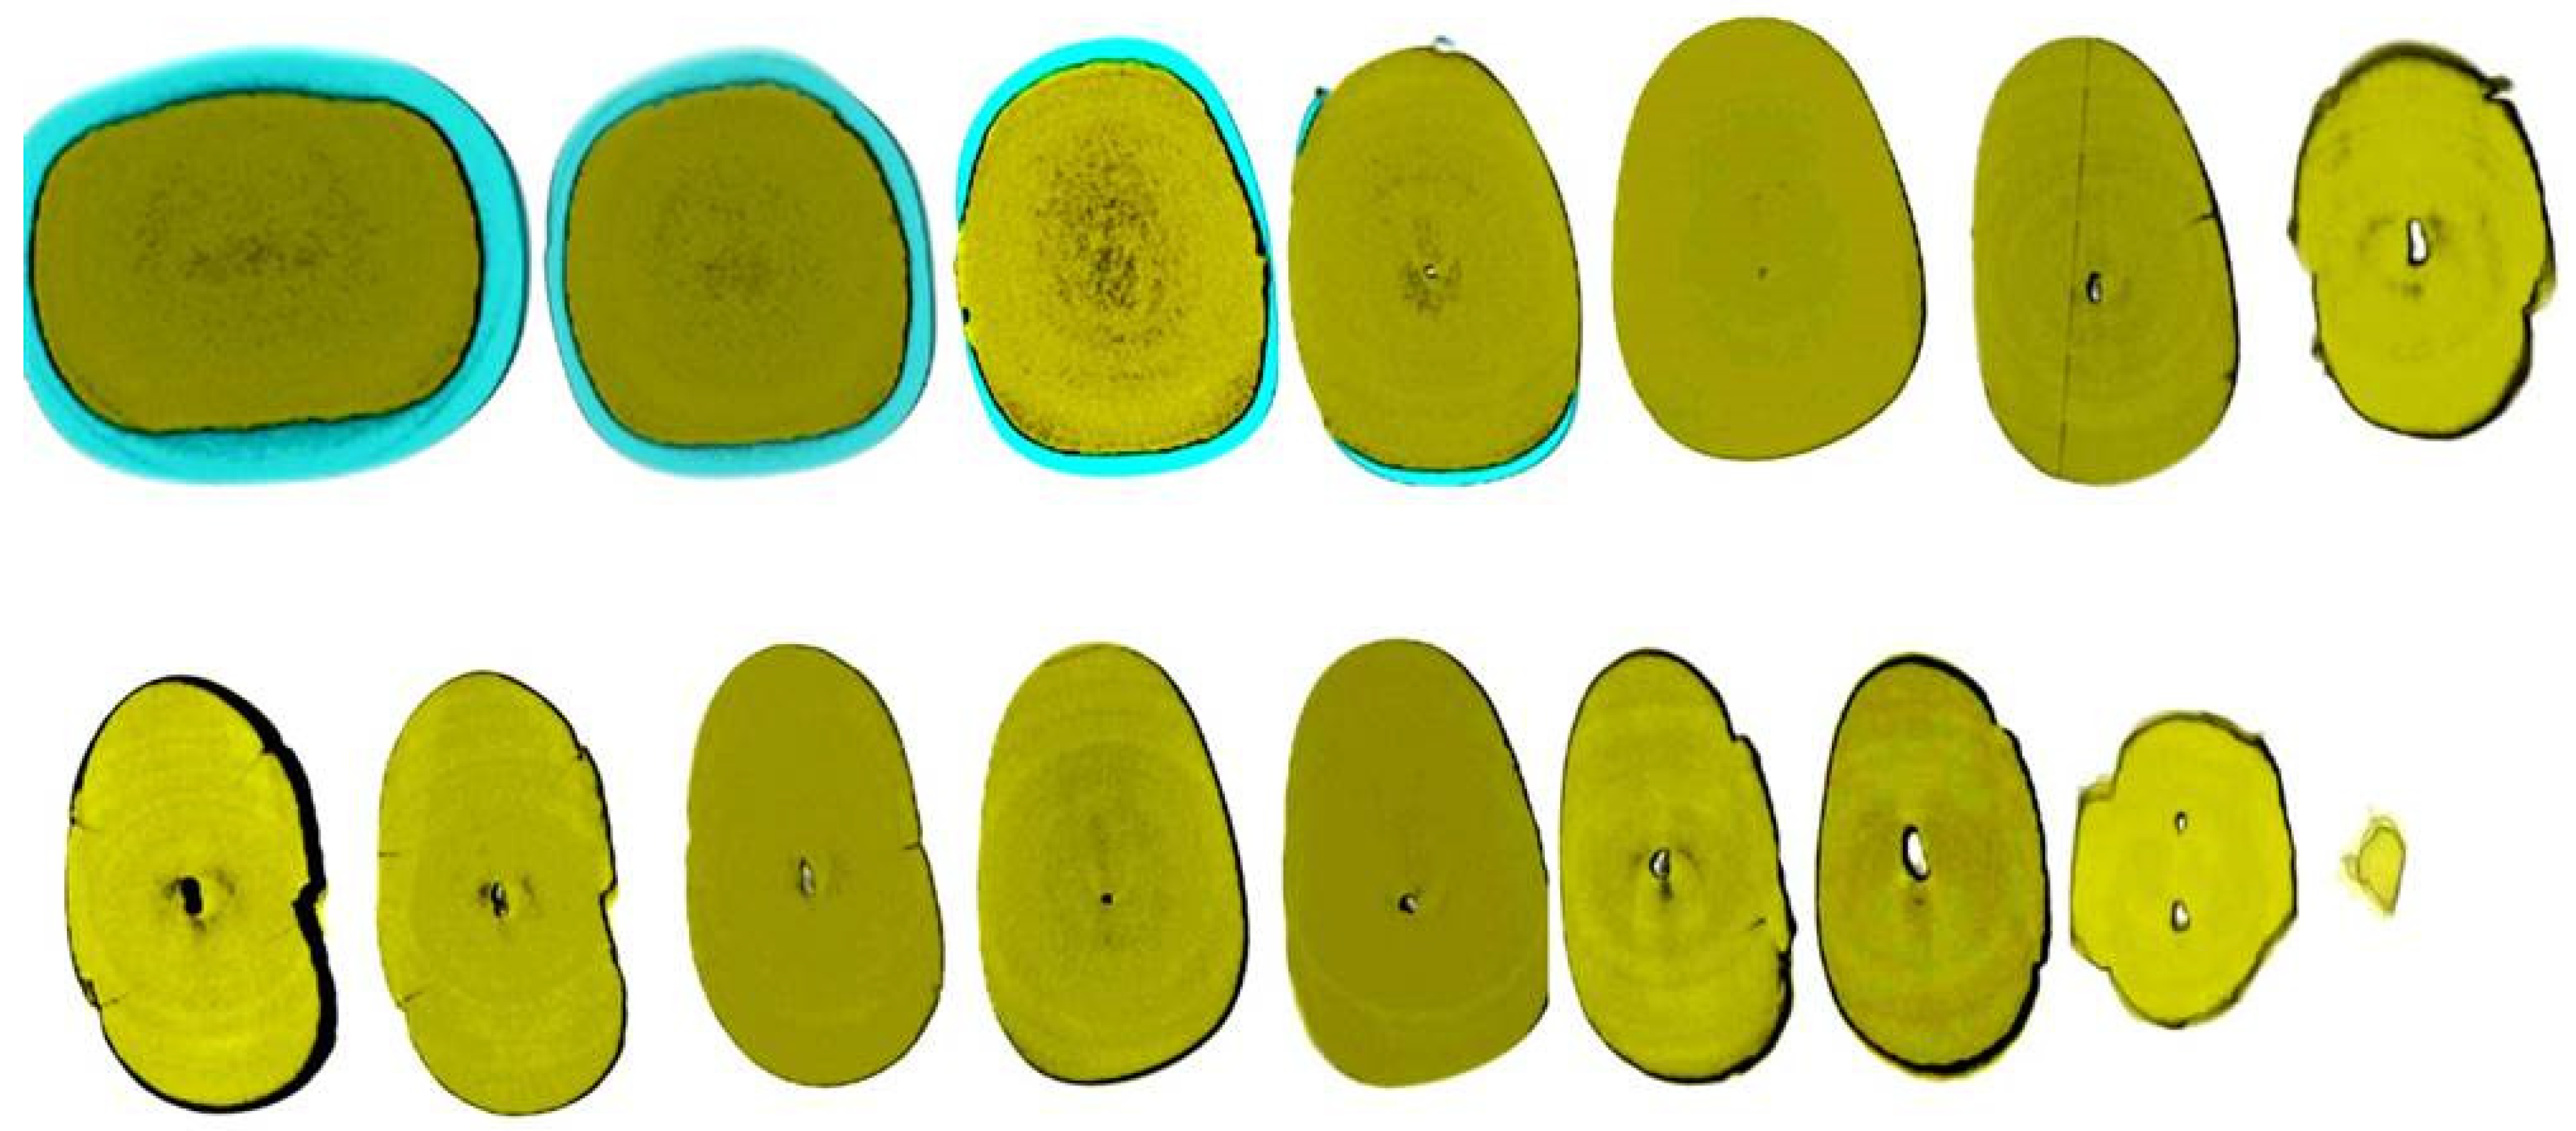

Figure 4.

Removal of a pulp stone from a second mandibular molar suffering from irreversible pulpitis. Micro-ct evaluation of the external and internal structure of the pulp stone. Notice that the structure of the pulp stone is not solid presenting an internal network of unmineralized tissue. The clinical significance is that the pulp stones can be dissected in smaller pieces and removed.